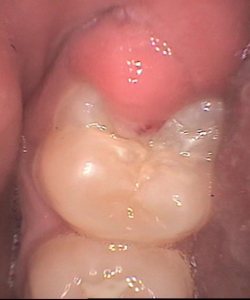

a close-up image of a gum flap over a lower wisdom tooth.flap of gum over a tooth

a wisdom tooth with a small gum flap and a small cavity on the biting surface.pericoronitis behind a wisdom tooth

In the image above, the tooth has almost grown into its final position. The flap of gum has become smaller. Now there's just that small cavity to deal with!